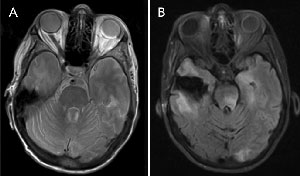

Magnetic resonance imaging (MRI) of the patient’s brain showed an area of encephalomalacia in keeping with her previous surgery. Inflammatory changes and a retinal detachment were noted in the left globe. The optic nerves appeared normal. No orbital masses were noted, and no cavernous sinus pathological features were observed (Box 2, A). A surgical vitreous biopsy was performed on her left eye.

She was commenced on intravenous aciclovir. A repeat MRI scan 8 days after the initial scan showed increased signal on flair involving the thalamus, occipital, temporal lobes and brainstem in keeping with an encephalitis (Box 2, B).